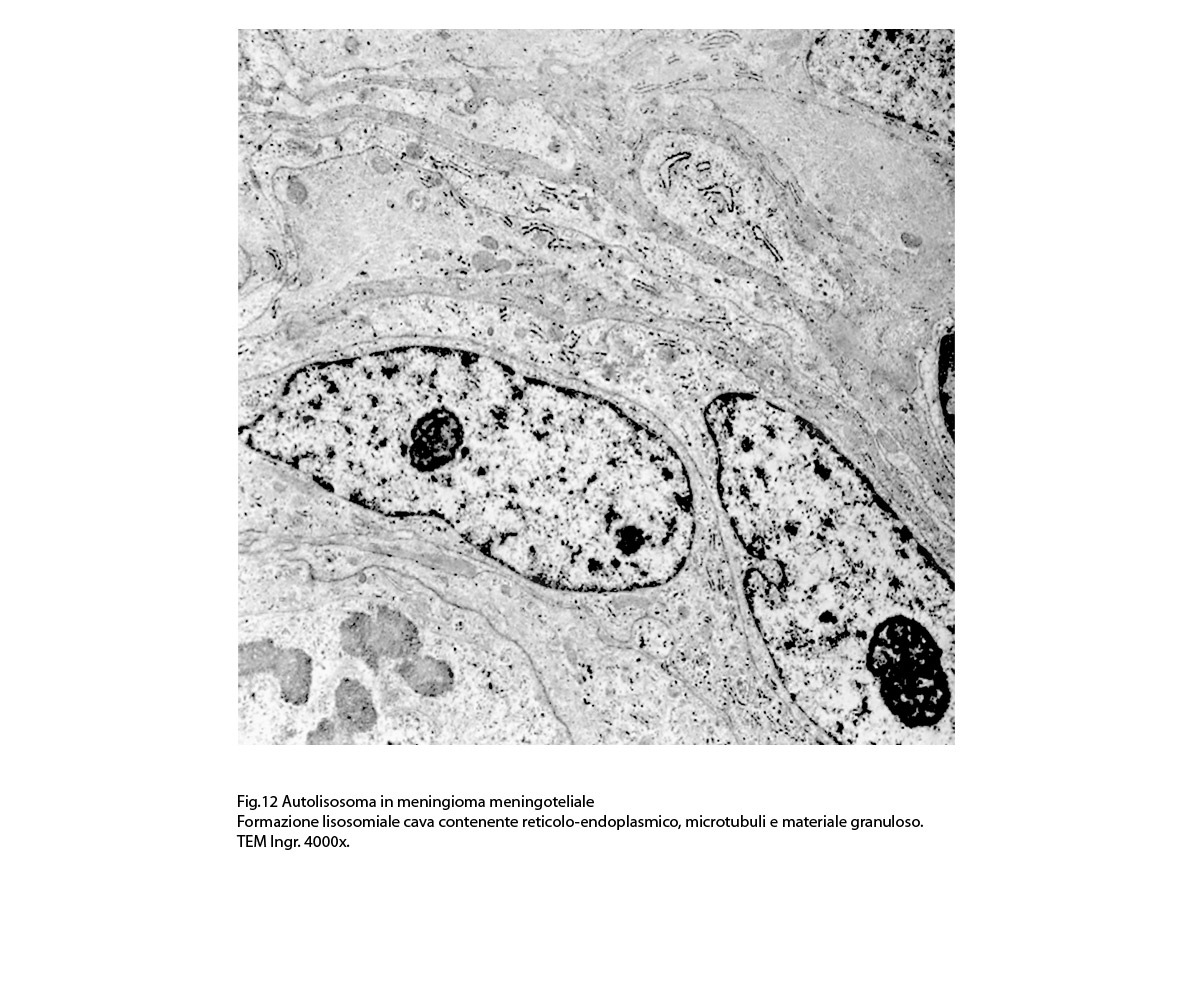

2/b AUTOLISOSOMA

Alcune cellule meningoteliali sono sedi, sopratutto a livello delle fasce periferiche, di ampie vescicole, di forma irregolare le quali sono demarcate da una membrana a mono-strato; gli spazi di queste vescicole sono in buona parte occupati da materiale amorfo, da frammenti filamentosi e da organuli intracitoplasmatici,tutto sottoposto a degradazione.

E’ possibile anche il reperto di elementi cellulari aventi il citoplasma occupato da ampie vescicole,delimitate da una membrana a monostrato, le quali sono ricolme di materiale amorfo,da strutture granulo-filamentose o da frammenti di organuli.

Non è raro il riscontro di cellule meningoteliali le quali hanno il citoplasma in buona parte occupato da una formazione cava,irregolarmente rotondeggiante; questa è delimitata da una spessa membrana ed è occupata da frammenti di citoplasma e da singoli organuli,tutto in corso di degradazione.

Nel contesto di alcune cellule coese,tutte contenenti focolai di micro e macroautofagia,è possibile rintracciare una di esse la quale è occupata da una ampia vescicola,a pareti frastagliate e lacerate, quasi ricolma di organuli e materiale filamentoso. Il citosol di tutte queste cellule è iperchiaro e gli organuli ivi contenuti sono in numero esiguo e mostrano segni morfologici di necrobiosi.